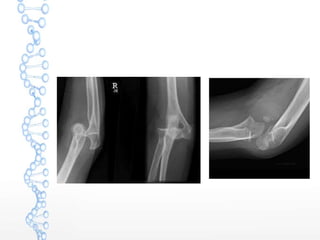

ELBOW DISLOCATION

 Accounts for 11% to 28% of injuries to elbow

 Posterior dislocation common

 Simple dislocations are associated with ligamentous

failure

 Complex dislocations are associated with fractures